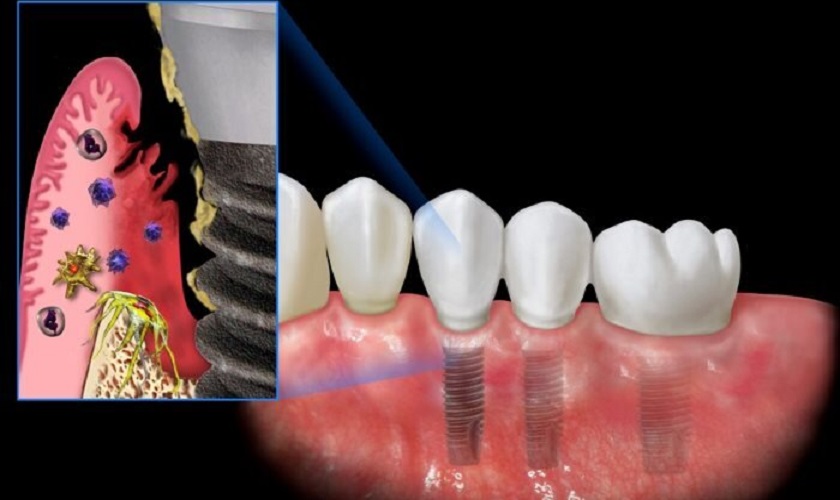

• Sức đề kháng yếu: Người bị tiểu đường thường có sức đề kháng kém, làm tăng nguy cơ nhiễm trùng sau khi cấy ghép Implant. Nhiễm trùng cao đồng nghĩa với nguy cơ thải ghép Implant cao.

• Rối loạn chuyển hóa: Tiểu đường nếu không được kiểm soát sẽ dẫn đến rối loạn chuyển hóa, ảnh hưởng đến chất lượng xương. Tế bào xương non bị giảm chất lượng, khiến quá trình tích hợp xương gặp khó khăn. Điều này làm tăng nguy cơ thất bại, thải ghép hoặc nhiễm trùng Implant.

người bị tiểu đường cấy implant dễ bị nhiễm trùngNgười bị tiểu đường cấy implant có khả năng bị nhiễm trùng